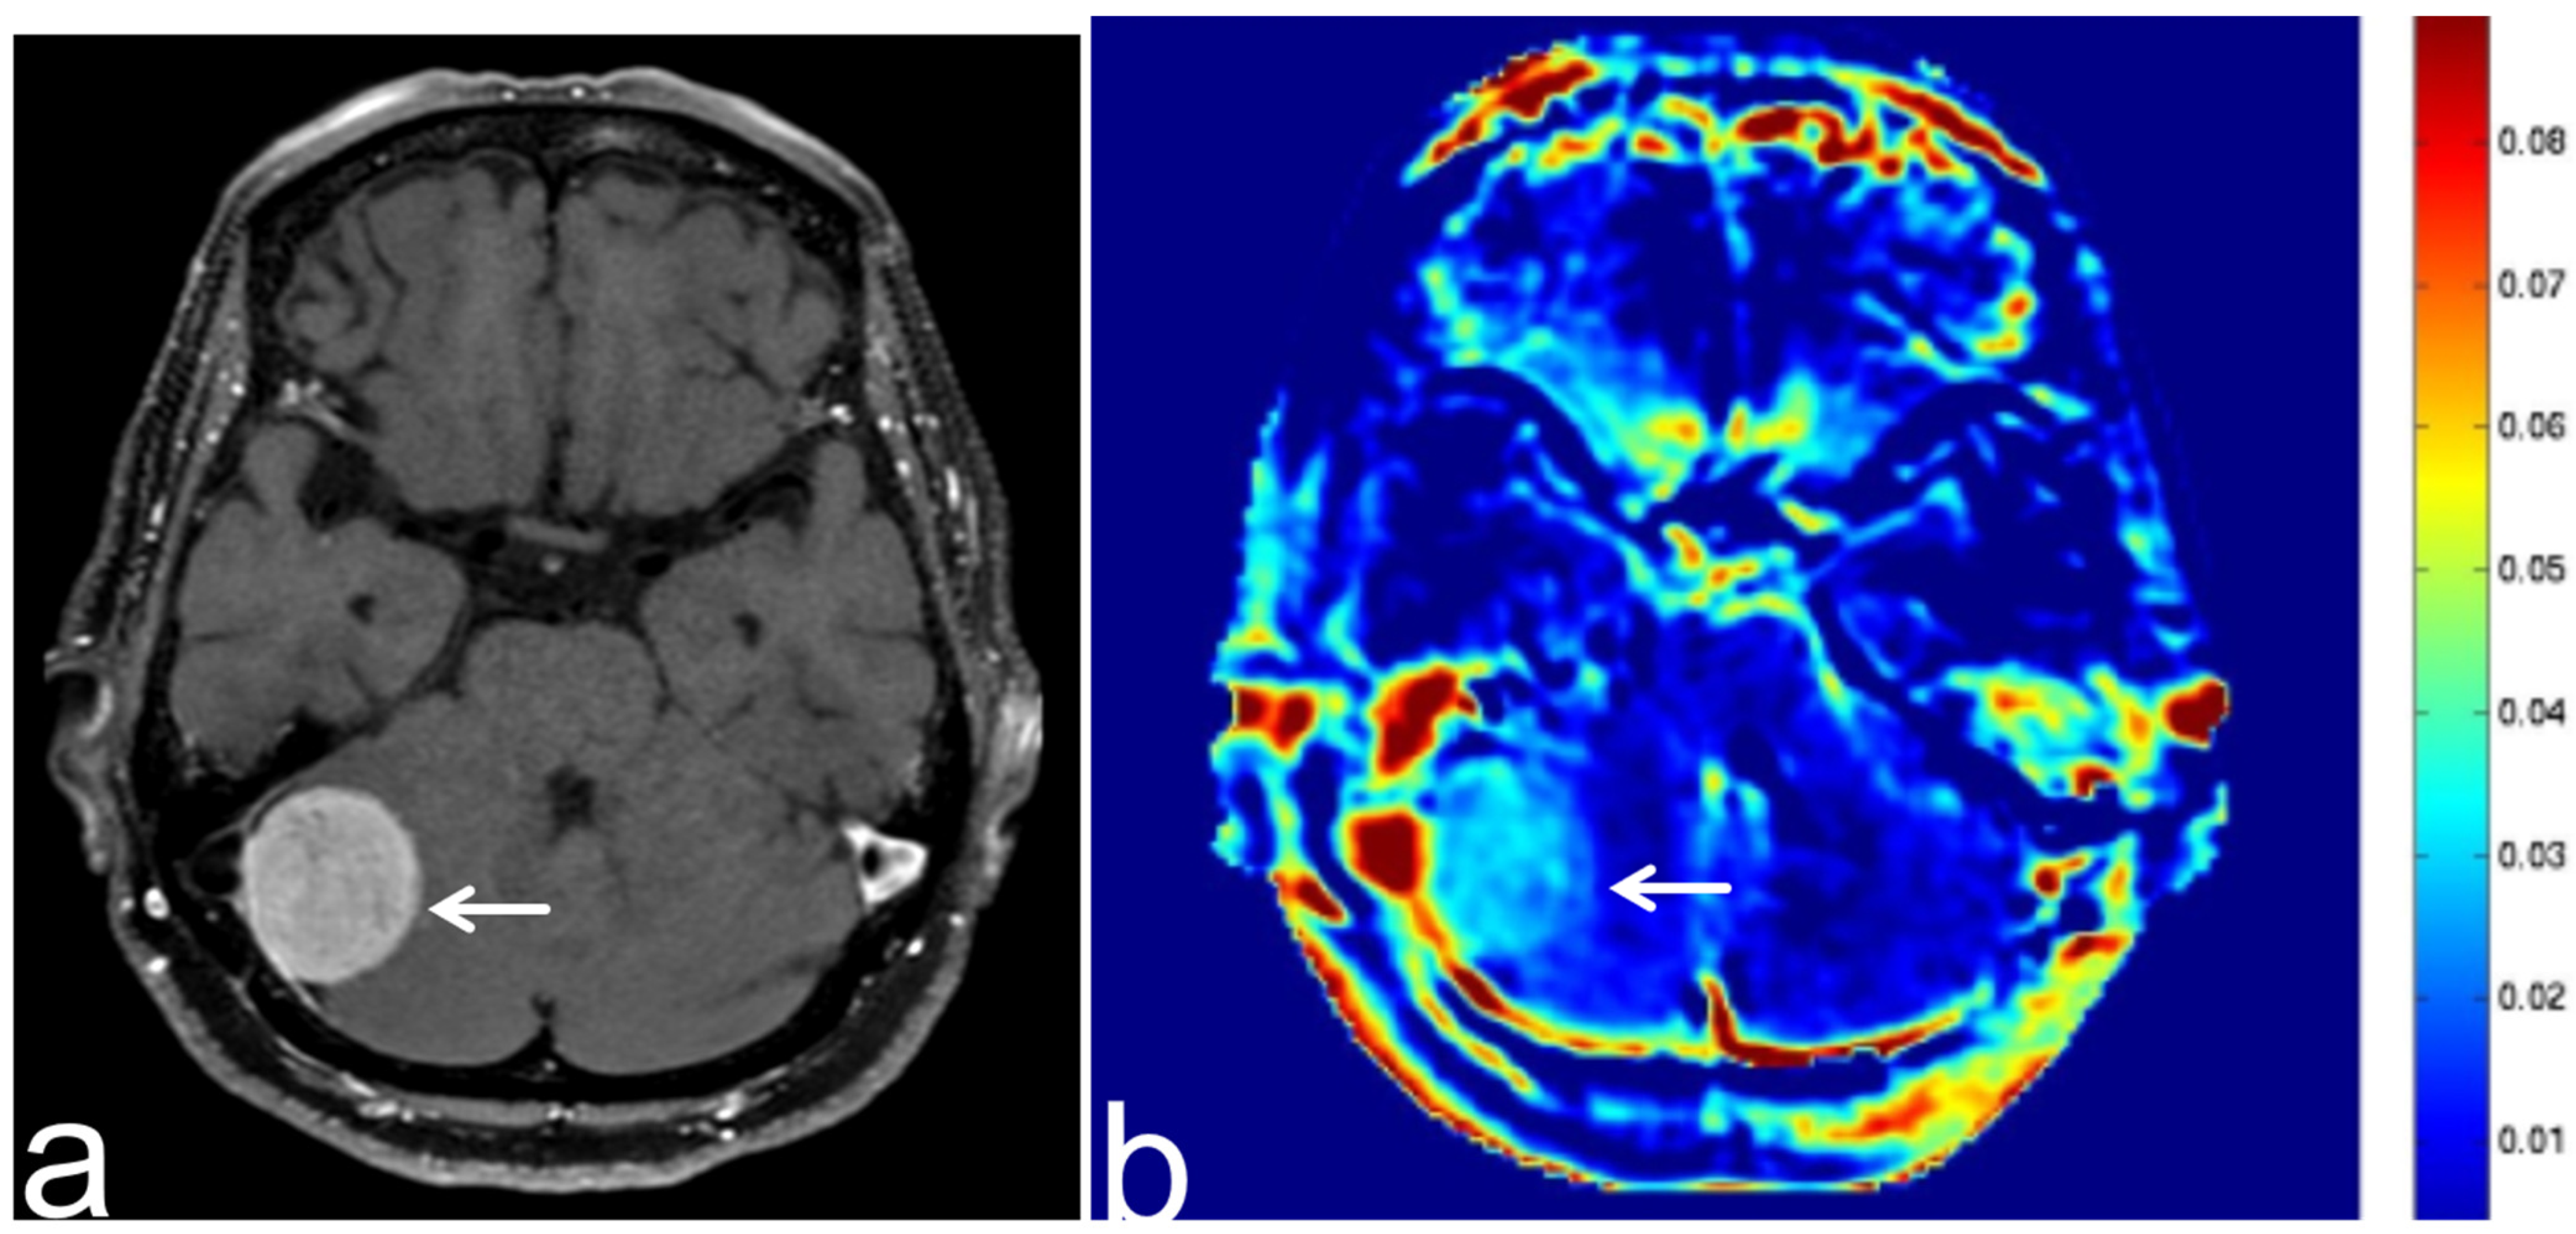

5.5. Brain Metastasis